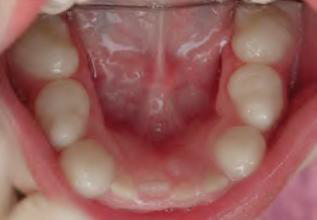

Gingival Cyst of the newborn | dental lamina rest | 新生兒上顎牙齦 ![]() |

- | 管腔內含有角質碎屑(keratinaceous debris) ![]() |

|